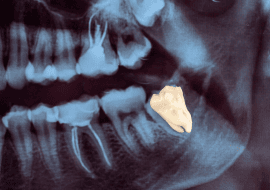

2. Dente incluso ou impactado

Se o siso fica preso dentro do osso ou gengiva (incluso), pode causar dor, infecções e até danificar os dentes vizinhos.